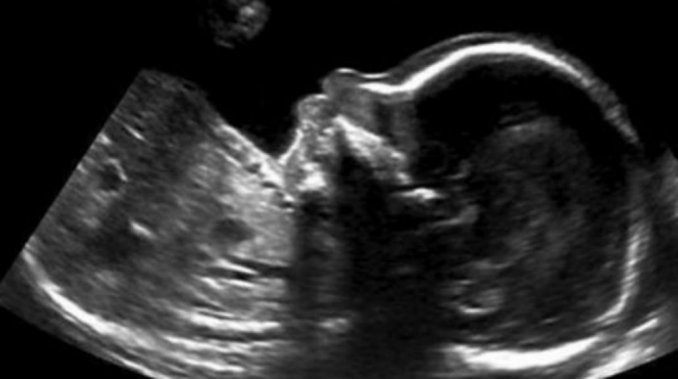

"Todo va bien", parece decir el bebè desde el vientre materno de la canadiense Nicole Kim. La mujer compartió en las redes sociales la foto y se hizo viral en pocas horas.

En la semana 20 y en uno de los controles de rutina, Nicole y Tony, el padrei, fueron a hacer la ecografía del cuarto mes de embarazo. Fue en ese momento que vieron cómo su hijo les daba un mensaje de aliento por la situación que estaban atravesando.

"Para mí era como un ´todo va a estar bien´.En Calgary, hay mucha gente sin trabajo ahora mismo y es duro para las familias. Conocemos otras dos que están en esa situación", relató Nicole quien además contó que ese mismo día sabían que quien estaba creciendo en su vientre,era un varón.